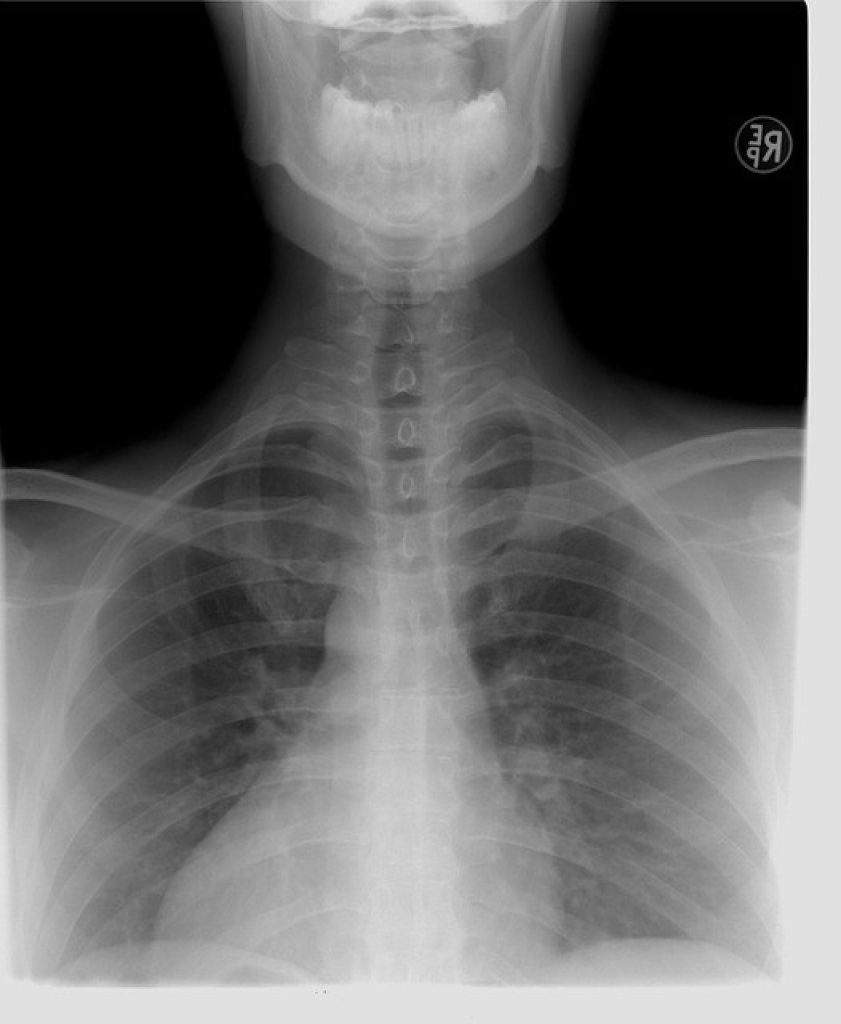

肺癌在台灣素有「三冠癌王」惡名,不僅發生人數多、死亡率高,且晚期確診比例更是居高不下,對國人健康構成重大威脅。胸腔科醫師蘇一峰沉重指出,這就是肺腺癌最可怕之處:「初期症狀不明顯,如果等到有症狀就醫時,十之八九通常都已經是末期!」他甚至分享有病患肺腺癌長到10公分,初期竟仍無明顯警訊。

醫師黃軒也將肺癌比喻為「沉默的獵人」,潛伏在胸腔深處,沒有疼痛、沒有警訊,等到民眾以為只是小感冒時,癌細胞早已築起堅固堡壘。根據國際研究,全球超過80%的肺癌患者在確診時已是第三或第四期。這意味著肺癌並非突然惡化,而是我們太晚察覺。

面對這位「隱形殺手」,專家共同提醒,定期篩檢是預防肺腺癌的最佳對策。特別是高危險群,應主動接受低劑量電腦斷層檢查,切勿輕忽身體的「沉默」,讓寶貴的黃金治療期悄悄溜走。